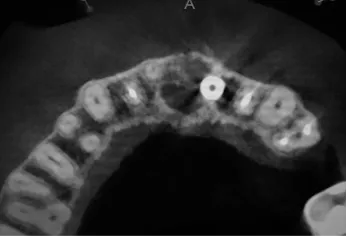

Precyzja projektu druku siatki bazuje na dokładności odwzorowania kształtu kości w stożkowej tomografii komputerowej CBCT, co zapewnia ich dobre przyleganie do podłoża kostnego oraz ogranicza powstawanie powikłań w postaci obnażania się siatek. Precyzja projektu oraz materiał, z którego wykonana jest siatka (biozgodny stop tytanu), powodują, że obnażenie się siatki nie zaburza procesu gojenia i regeneracji kostnej.

Wymaga jedynie większej ilości kontroli pozabiegowych oraz wzmaga czujność higieniczną zarówno ze strony lekarza, jak i pacjenta. Ten rodzaj odbudowy kostnej stosowany jest w sytuacjach złożonych, trójwymiarowych 3D ubytków kości, przy których standardowe metody odbudowy są niewystarczające. Ilość kości, którą możemy uzyskać, stosując tę metodę, to nawet kilka centymetrów sześciennych.

Metoda rekonstrukcji kostnej w oparciu o indywidualnie drukowane siatki z tytanu dla implantacji wszczepów śródkostnych stosowana jest najczęściej jako dwuetapowa. W pierwszym etapie odbudowywana jest kość, natomiast implanty wszczepiane są po okresie 4–6 miesięcy. Na wgojenie implantów oczekujemy od 4 do 6 miesięcy w zależności od miejsca ich lokalizacji. Siatka tytanowa po spełnieniu swojej funkcji rusztowania dla odbudowującej się kości jest następnie usuwana w dniu wszczepienia implantu. Jeżeli kość spełnia odpowiednie warunki, istnieje możliwość zastosowania modyfikacji siatki tytanowej, która umożliwia jednoczesne wprowadzenie implantów wraz z odbudową kostną.